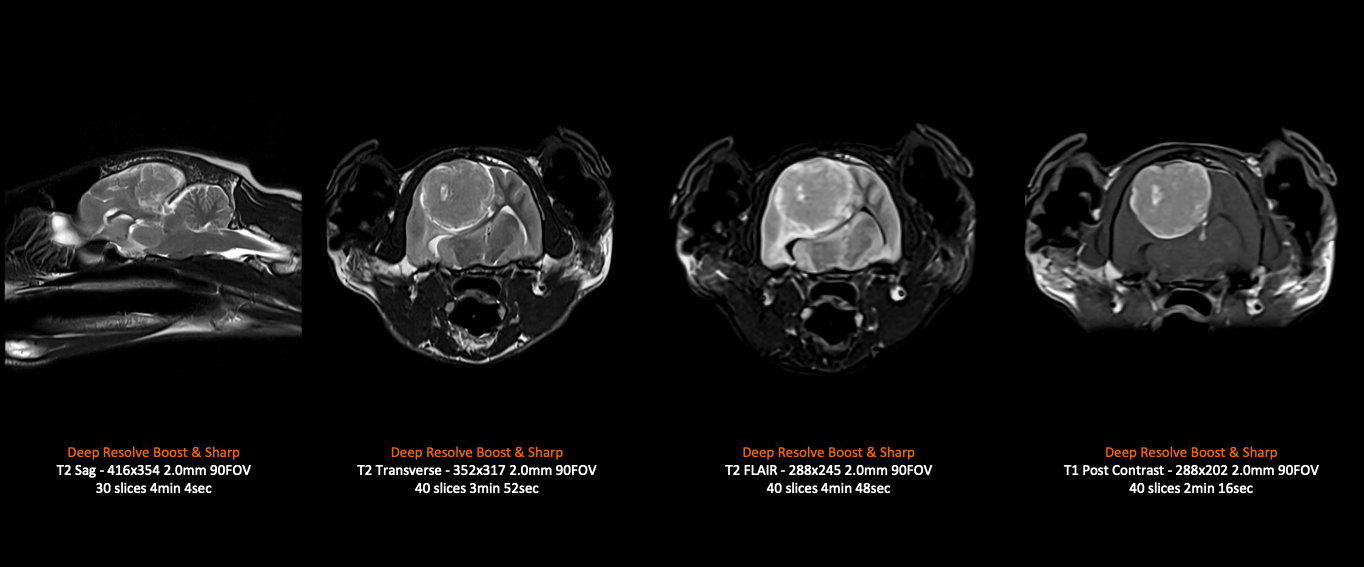

The intuitive AI-based software can be tailored to the specific needs of Vet imaging, with simplified and guided workflows. Incorporating our latest deep learning technology, Deep Resolve, examination times are shortened yet with higher image resolution. This means anesthetic times can be reduced, and less stress on our furry friends. The system includes lightweight and flexible coils perfectly suited for high quality animal imaging and providing the best care and comfort. The MAGNETOM Sempra is distinguished by its low operating costs with zero-helium boil-off and integrated Eco technologies that saves power to reduce overhead costs.